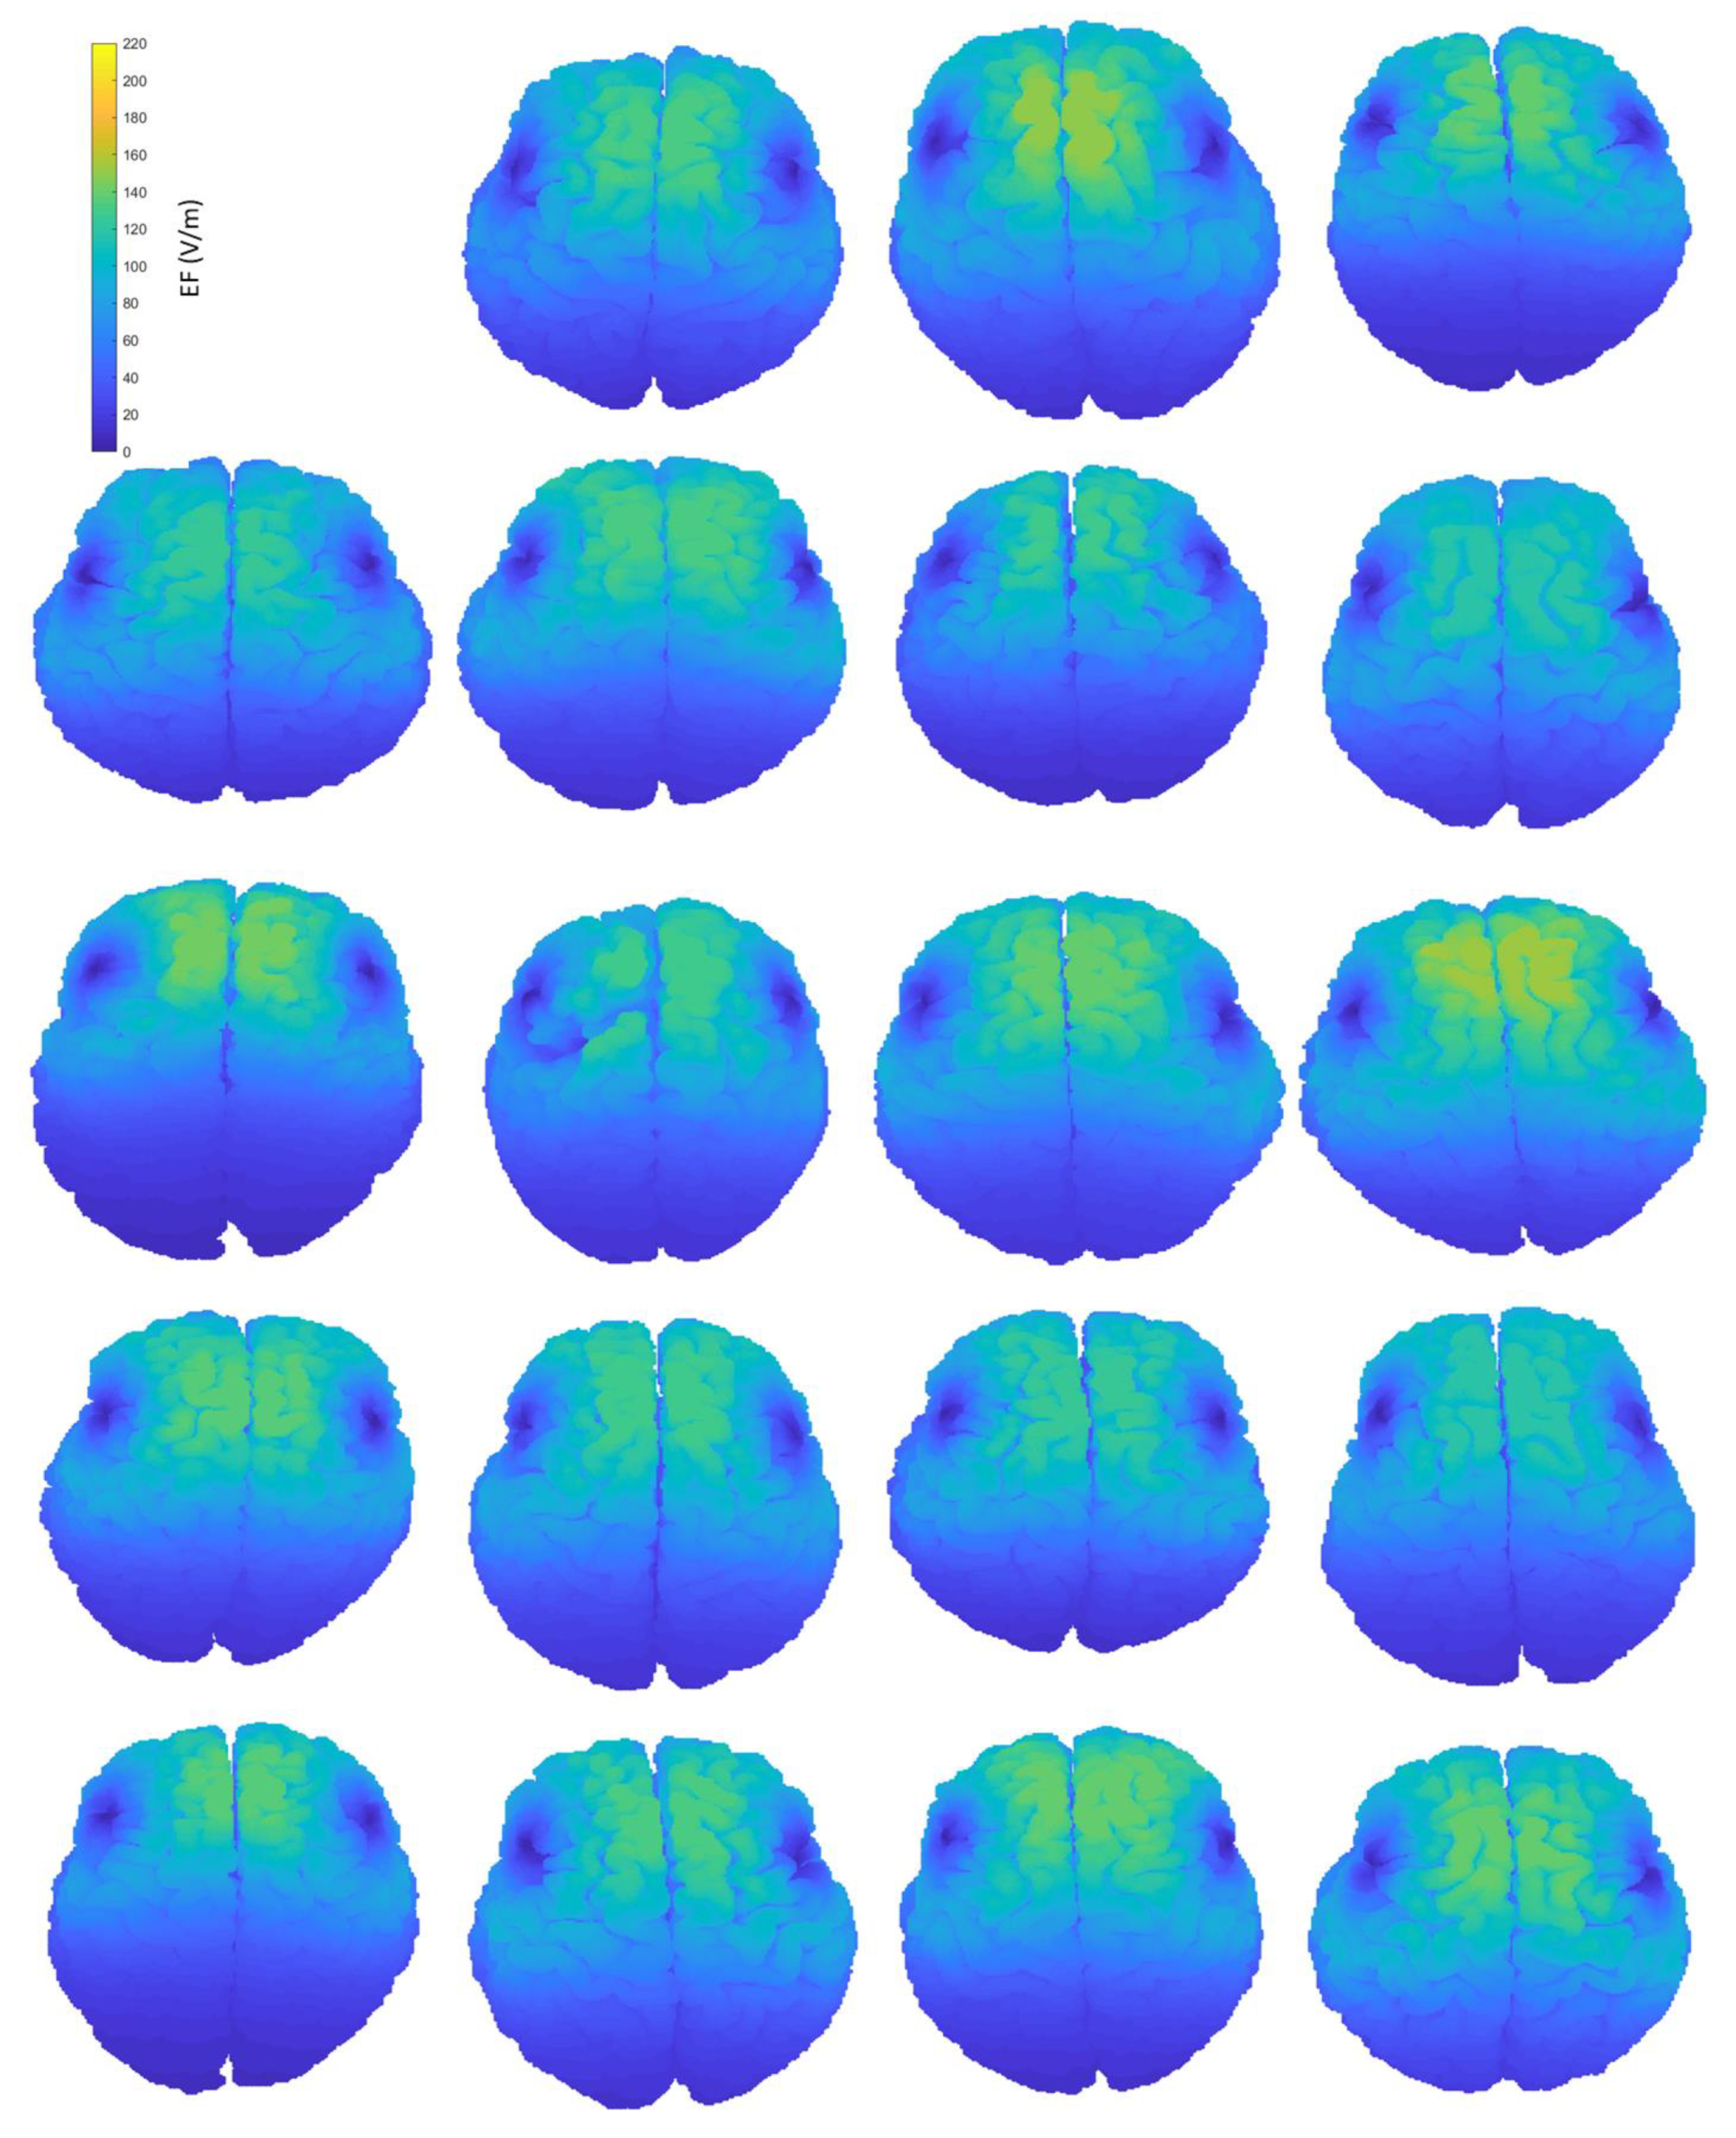

Figure A2.

Interindividual variability of the induced EF distributions visualized on subjects’ homogeneous brains, containing both grey and white matter, when the coil is placed at frontal position.